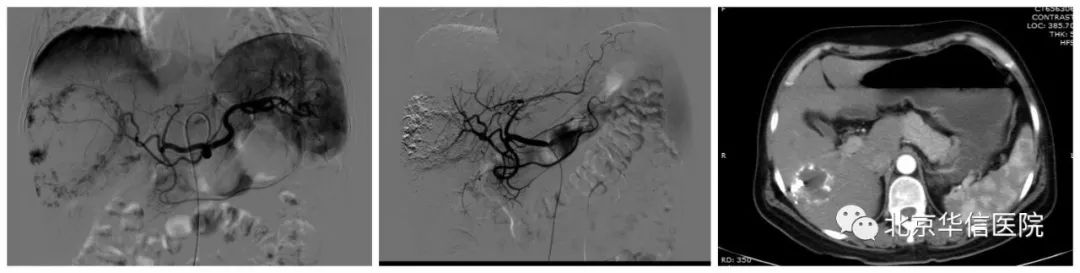

左图:栓塞前造影;中图:栓塞后造影;右图:栓塞后九个月复查CT

随后,我们采取了肝动脉造影及栓塞的方法进行治疗,经过患者右侧大腿根部不够1mm的穿刺点,将导管沿股动脉血管送入肝动脉,通过造影可见巨大的典型血管瘤染色。经微导管直接挑选肿瘤的供血血管,避开正常肝脏的供血血管,在治疗肿瘤的同时最大程度地保护正常的肝组织。栓塞完成后可见肿瘤内充满了用于治疗的碘油乳剂,而正常的肝血管、肝组织没有受到药物影响。3个月后患者通过CT复查,以前巨大的肿瘤迅速缩小到不够3cm,一切不适已完全消失。最重要的是,患者没有开刀、没有失血,仅仅通过创口还不够1mm、用时不到30分钟的微创介入手术,就达到了令患者满意的治疗效果。